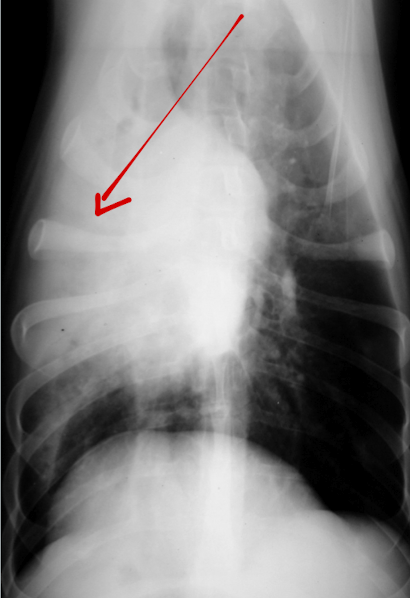

What lung pattern? What is the arrow pointing to?

Alveolar pattern

lobar sign